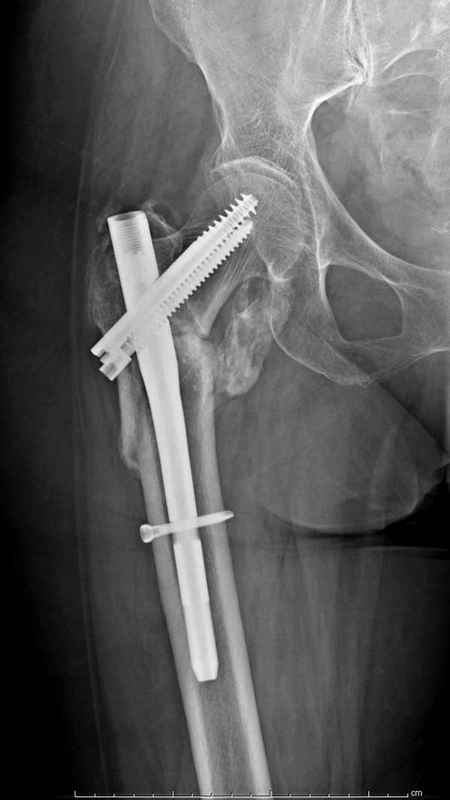

[Ortho] Чрезвертельный перелом бедра

Здесь 83 года, травма в результате падения

Имя     : Hip final.jpg

Тип     : image/jpeg

Размер  : 29097 байтов

Описание: отсутствует

Url     : http://weborto.net:8080/pipermail/ortho/attachments/20090826/208099a1/attachment-0012.jpg